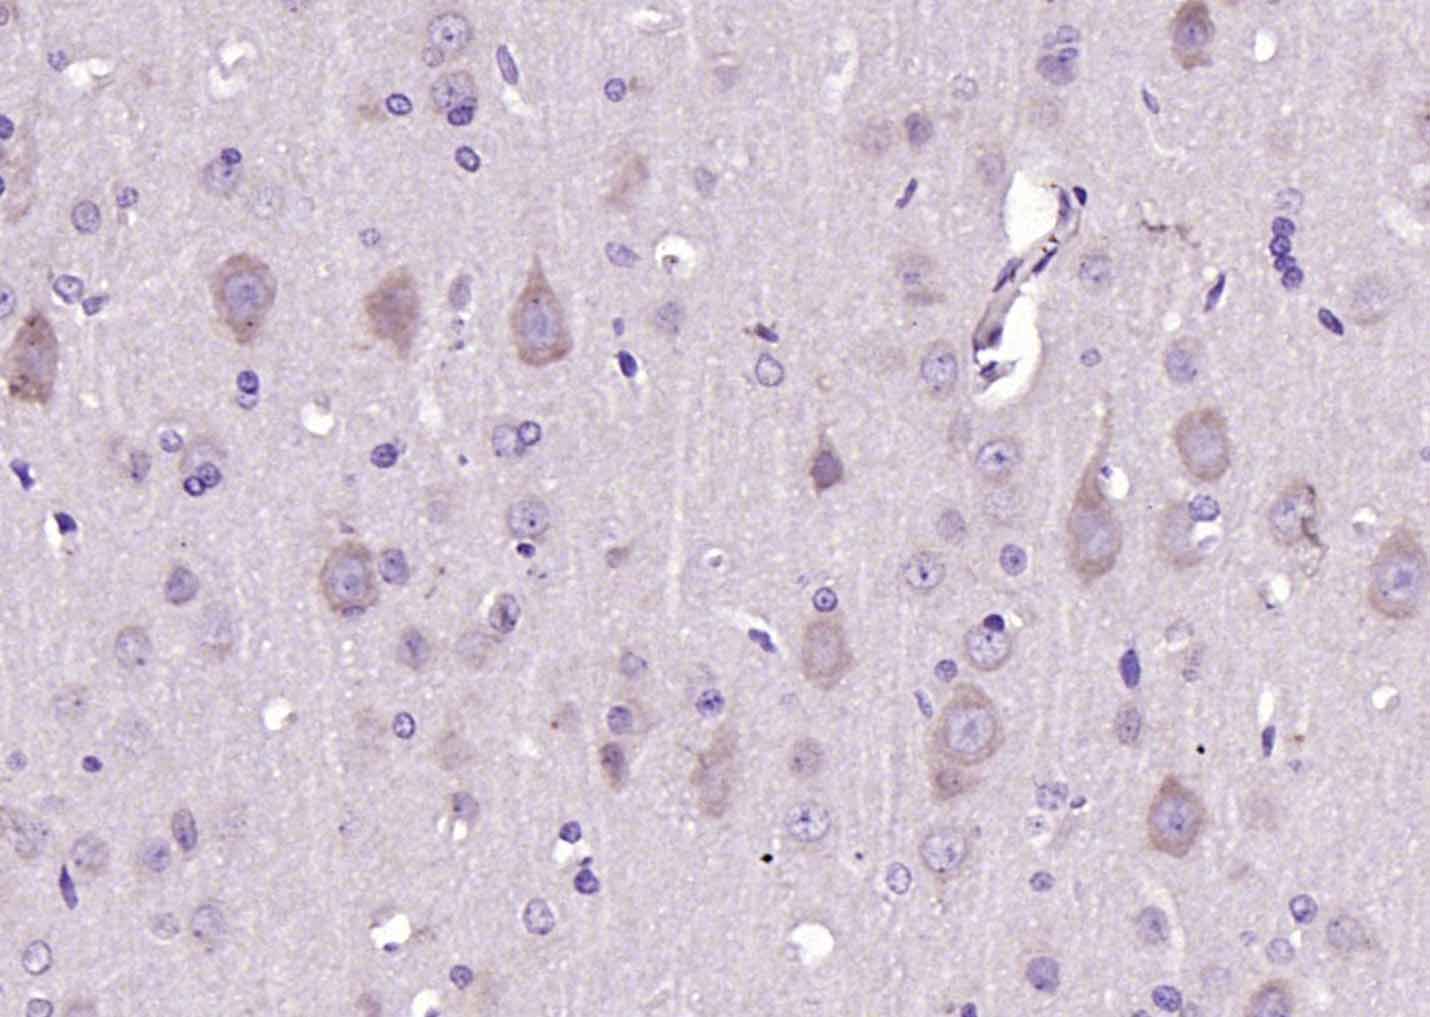

Paraformaldehyde-fixed, paraffin embedded (rat brain); Antigen retrieval by boiling in sodium citrate buffer (pH6.0) for 15min; Block endogenous peroxidase by 3% hydrogen peroxide for 20 minutes; Blocking buffer (normal goat serum) at 37°C for 30min; Antibody incubation with (Dopamine Receptor D1) Polyclonal Antibody, Unconjugated (bs-10612R) at 1:200 overnight at 4°C, followed by operating according to SP Kit(Rabbit) (sp-0023) instructionsand DAB staining.

Paraformaldehyde-fixed, paraffin embedded (Rat brain); Antigen retrieval by boiling in sodium citrate buffer (pH6.0) for 15min; Block endogenous peroxidase by 3% hydrogen peroxide for 20 minutes; Blocking buffer (normal goat serum) at 37°C for 30min; Antibody incubation with (Dopamine Receptor D1) Polyclonal Antibody, Unconjugated (bs-10612R) at 1:400 overnight at 4°C, followed by operating according to SP Kit(Rabbit) (sp-0023) instructionsand DAB staining.

Paraformaldehyde-fixed, paraffin embedded (Mouse brain); Antigen retrieval by boiling in sodium citrate buffer (pH6.0) for 15min; Block endogenous peroxidase by 3% hydrogen peroxide for 20 minutes; Blocking buffer (normal goat serum) at 37°C for 30min; Antibody incubation with (Dopamine Receptor D1) Polyclonal Antibody, Unconjugated (bs-10612R) at 1:400 overnight at 4°C, followed by operating according to SP Kit(Rabbit) (sp-0023) instructionsand DAB staining.